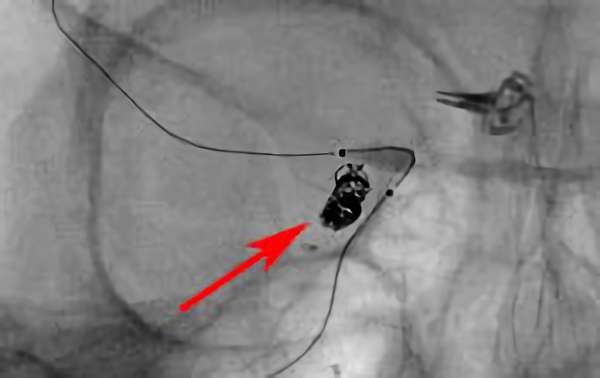

'26年4月

くも膜下出血

右内頚動脈瘤破裂

30代

救急外来

No.1626 手術前

No.1626 手術中

No.1626 手術後